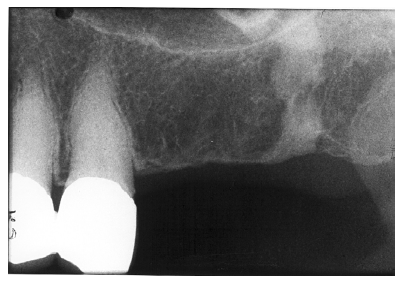

Figure 2 - Advanced Enamel Caries

Figure 2

Figure 2 illustrates advanced enamel caries on the mesial surface of the premolar.